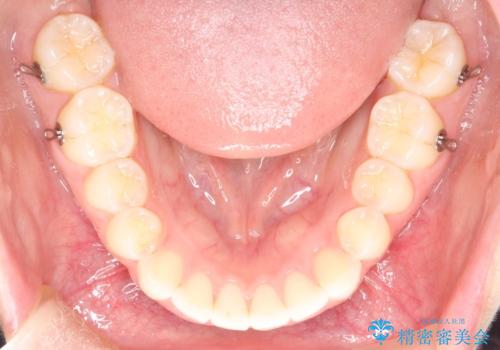

【インビザライン】前歯が出ているのを治したい

- 前歯が出ていることを主訴に来院されました。

前歯の突出感が改善され、満足していただきました。

インビザラインは20時間以上の使用が必要です。